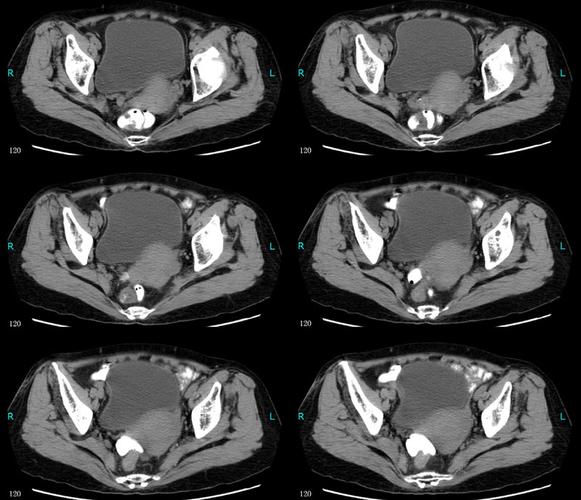

术前ct见膀胱左侧壁占位.